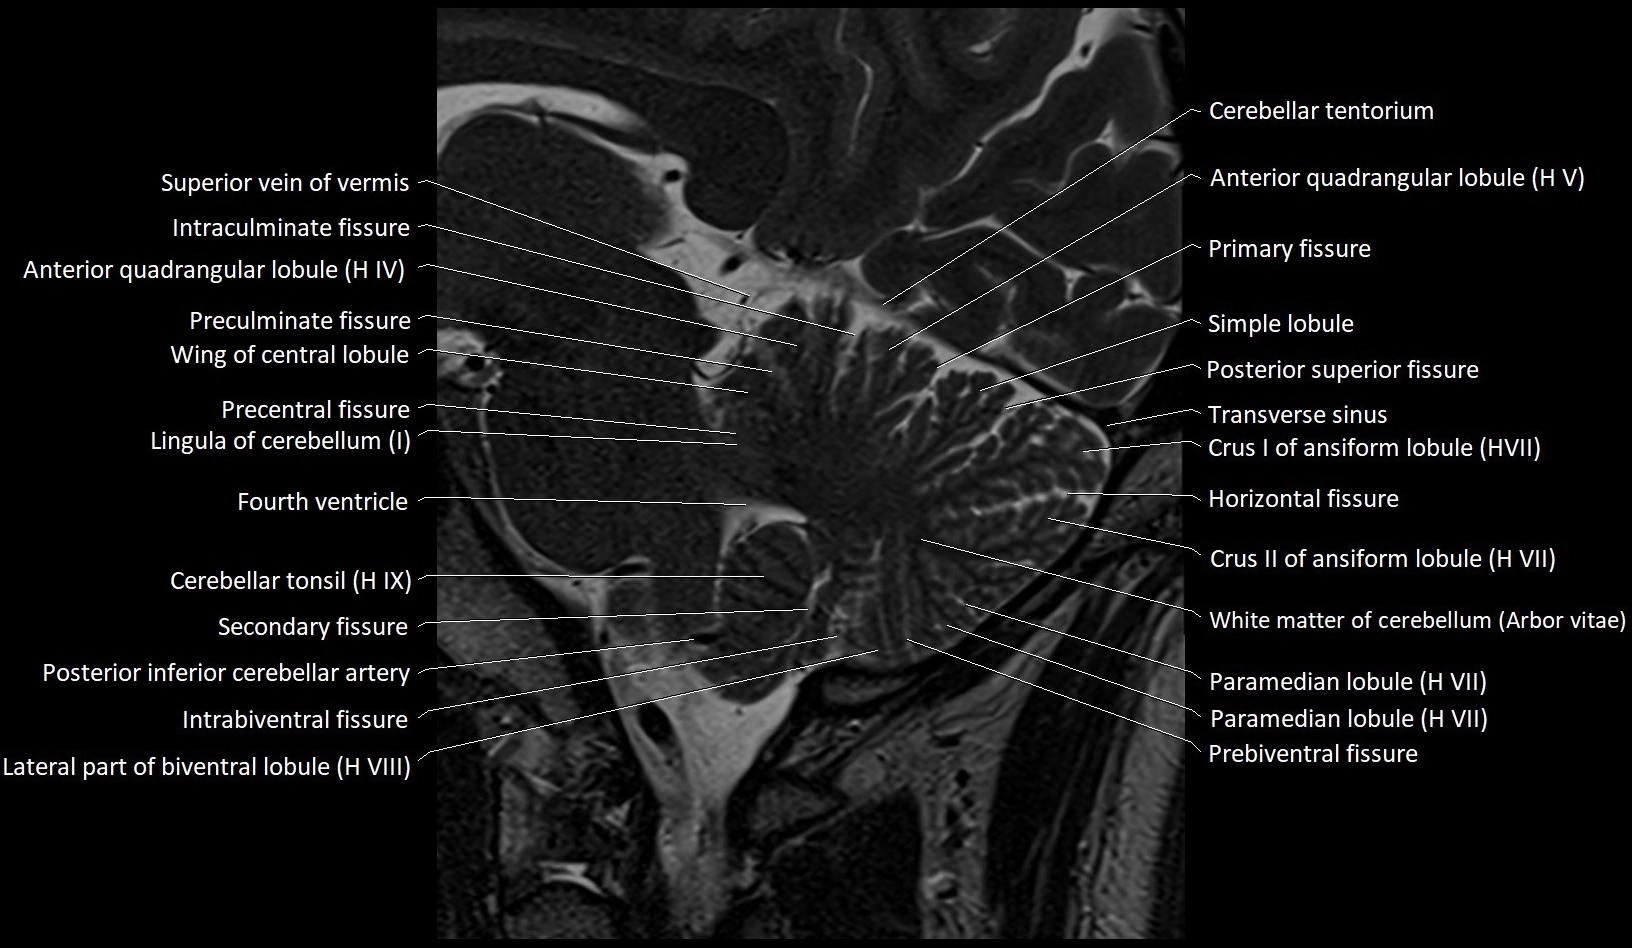

MRI images